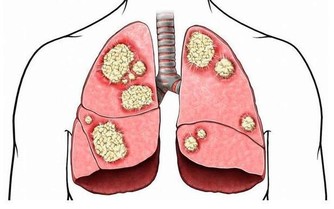

鞋子穿久了腳指甲通常會有內翻的情況,又稱指甲內生,

但其實正確來說是「甲溝炎」、「凍甲」。

當這個情況發生的時候,因為指甲會夾到肉,感覺非常痛。

如果狀況比較糟糕的話,會發生發炎、化膿的情況,而且會痛到讓人無法走路喔!